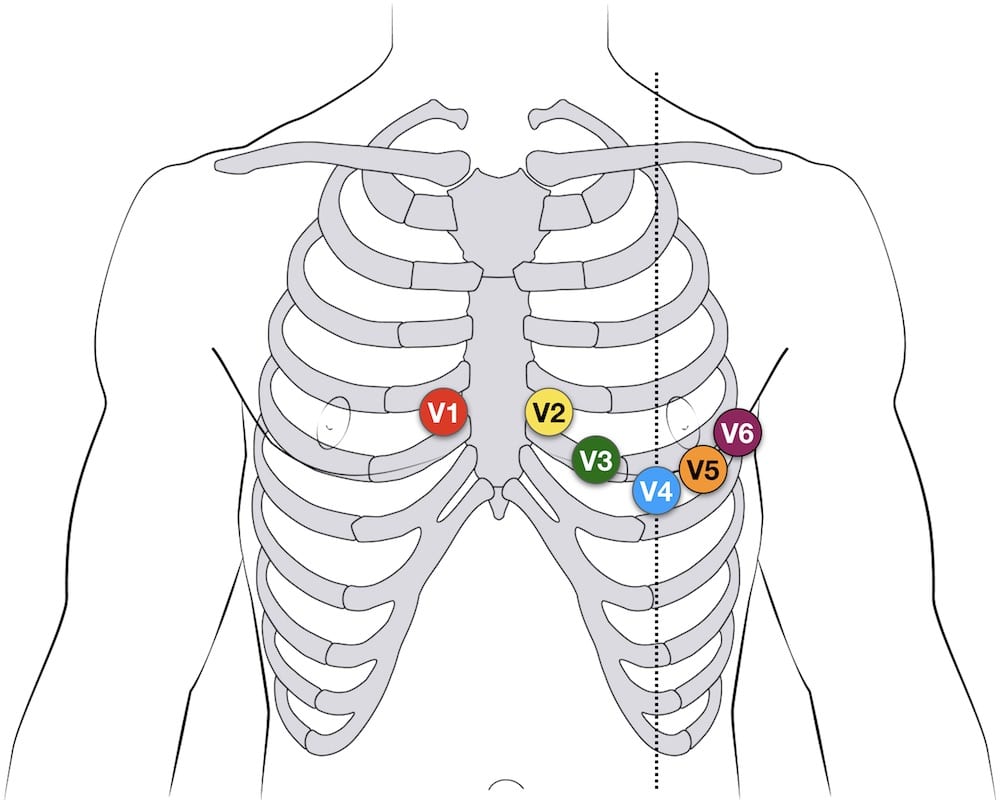

3. Waveforms, Segments, and Intervals

This illustration nicely outlines and summarises the various waveforms, segments and intervals:

This table only included the clinically and exam-important information (e.g. extra information like normal amplitude of the waves is omitted):

| Wave / segment / interval | Definition | Underlying mechanism | Normal duration / morphology |

|---|---|---|---|

| P wave | First small +ve deflection before QRS | Atrial depolarisation |

|

| PR interval | Start of the P wave → start of QRS | Conduction through the AV node |

|

| QRS complex | Series of deflections after the PR interval

|

Overall: ventricular depolarisation

|

Not all the components of the QRS complex are always seen:

|

| ST segment | End of QRS (J point) → start of T wave | Time when the ventricles are all depolarised |

|

| T wave | Deflection after the ST segment | Ventricular repolarisation |

|

| QT interval | Start of QRS → end of T wave | Ventricular depolarisation and repolarisation | General duration:

The QT interval is inversely proportional to heart rate

**Students would generally not be expected to manually calculate the QTc interval in exams. The cutoff for normal QTc values varies depending on the source and method of calculation, so it is sufficient for exam purposes to learn a rough cutoff value, typically around 440–460 ms. If the exam question intends to indicate a prolonged QTc interval, it would usually be obvious with a clearly prolonged value such as 500 ms, rather than a borderline value like 470 ms. |